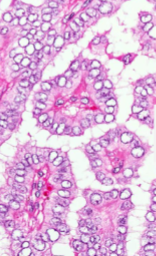

Graves Disease

Dilated follicles lined by increased numbers of tall follicular cells with papillary infoldings

Scalloped colloid (↑ pinocytosis of colloid)